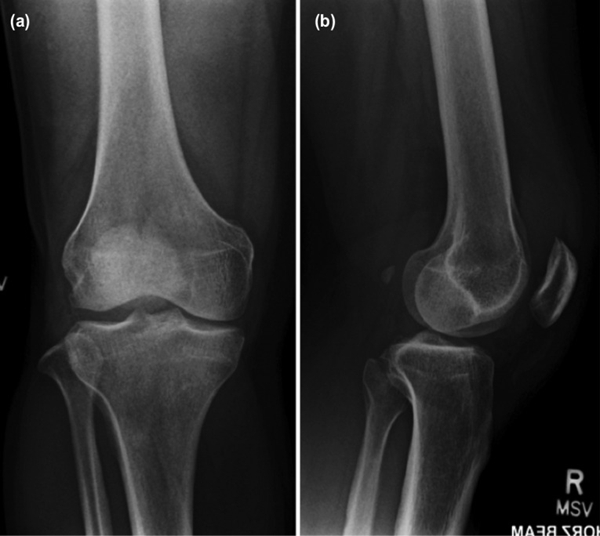

右膝X线检查显示退行性改变,并伴有内侧间室轻度狭窄(图1),关节内未见钙化。

(图1 右膝关节X线检查)